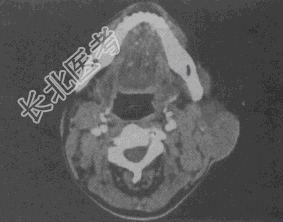

- 单项选择题女,25岁, 发现双侧颈部肿块近10年,CT如图, 最可能的诊断为

A、巨淋巴结增生症

B、淋巴瘤

C、转移瘤

D、淋巴结结核

E、淋巴结炎